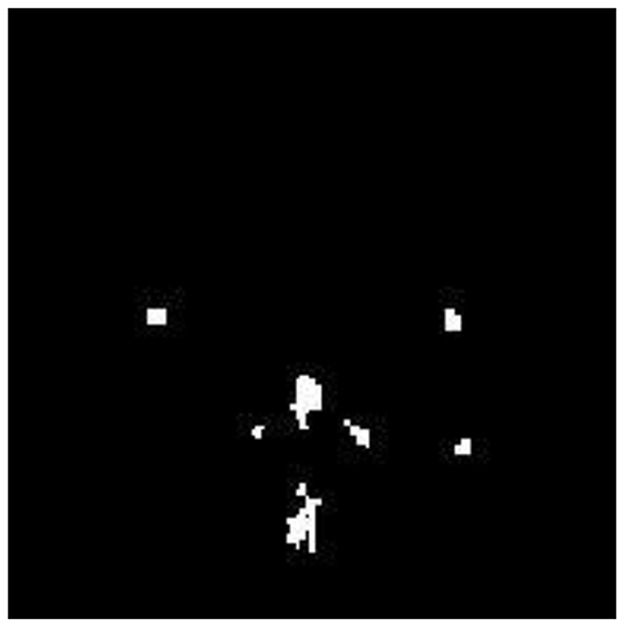

The FMA uses the detected AD image as its input image. Functional Morphological Dilation (FMD) is applied to the AD image using a disk-shaped structuring element with a radius of 0.5 mm, which increases or expands the outlier boundary of each pixel. The same image is then subjected to Functional Morphological Erosion (FME) using the same structuring element, which shrinks the outlier boundary of each pixel. AP pixels are detected and segmented in the AD image by subtracting the EI from DI. Figure 7 illustrates the segmentation of Alzheimer-affected pixel (AP) regions in an AD brain image, as classified by the RECNN model.

Figure 7. Segmentation output highlighting Alzheimer's-affected pixel (AP) regions in an AD brain image.

These segmented AP regions in the classified AD image are input into the RECNN classification algorithm for further analysis. Specifically, AP pixels from mild AD images and AP pixels from advanced AD images are trained separately by the RECNN algorithm to produce individual training patterns (ITPs). During testing, the AP regions in the classified AD image are processed by the RECNN algorithm against the ITPs, producing an output classified as either mild or advanced AD. Figures 8a, b present the simulation results from the testing phase, illustrating detection and classification outcomes for both AD and non-AD images. The results from each module are visualized through a graphical user interface.